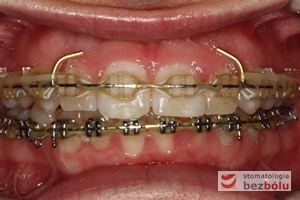

Pacjentka lat 22 zgłosiła się do naszej placówki celem podjęcia leczenia ortodontycznego. Głównym oczekiwaniem pacjentki była poprawa estetyki uśmiechu oraz brak ekstrakcji zębów na drodze do jej uzyskania. Ze względu na liczne stłoczenia zębów w górnym i dolnym łuku, dość duży materiał zębowy w porównaniu z bazą kostną, a także zgryz przewieszony boczny prawostronny po dokładnej analizie cefalometrycznej oraz analizie modeli diagnostycznych zastosowano leczenie bezekstrakcyjne z wykorzystaniem strippingu jako alternatywy dla usuwania zębów, mającego na celu uzyskanie miejsca w łuku na uszeregowanie zębów. Po fazie aktywnego leczenia trwającego 18 miesięcy zastosowano leczenie retencyjne w postaci szyny retencyjnej w łuku górnym oraz retainera stałego w łuku zębowym dolnym klejonego od kła do kła.